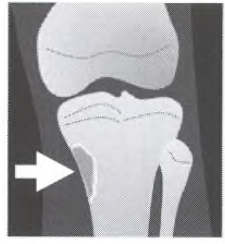

Giant Cell Tumor (GCT) Key Criteria - Physis MUST be closed - Non Sclerotic Border - Abuts the articular surface

20-30 = physis closed (MUST) Location: Knee - Most common Association: ABC (can turn into them) Quasi malignant (5% - lung mets) Fluid levels on MRI